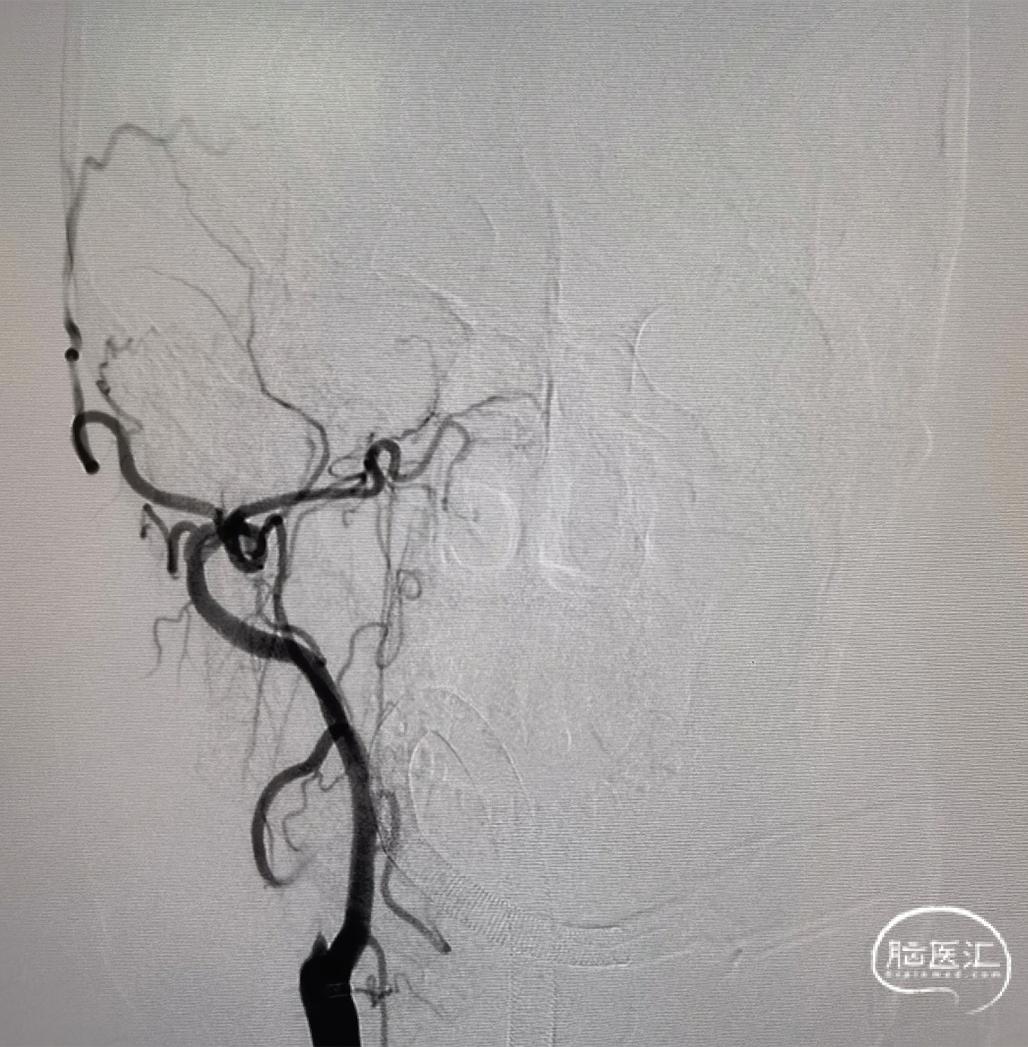

右侧颈总正侧位:见右侧颈内动脉闭塞,颅外血管代偿良好。

左颈总正侧位:左侧颈内动脉闭塞,可见血管残端。